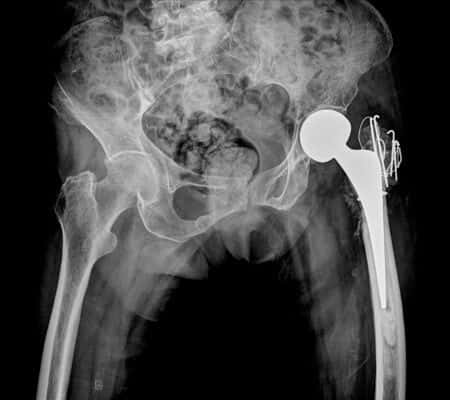

This defense case involves a sixty-two-year-old male patient who underwent a left hip arthroplasty. On postoperative day three, prior to transfer to a step-down facility, the patient alleged that he fell when walking to the restroom. The nurse charted and maintained that the patient never fell but, instead, that he became weak between the bathroom and bed and was gently guided to the floor. The physician was informed of the incident and told the nurse to let the receiving facility know that fall precautions were necessary. The patient was transferred to a long-term care facility for rehabilitation and complained of pain for the following three days. He was then transferred back to the hospital, where X-rays revealed dislocation of the new, prosthetic hip. A closed reduction was performed to place the man’s hip back into place.